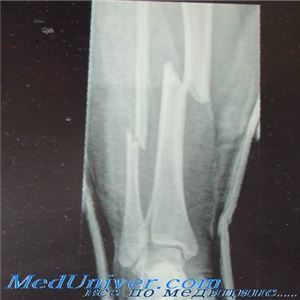

Представить энергию травмирующей силы можно на основании обстоятельств травмы и вида перелома. Раздробление кости (наличие более двух костных фрагментов) предполагает воздействие высокоэнергетической силы и сложную линию перелома. Косвенно указывают на количество поглощенной энергии переломы со смещением, а также обширные повреждения мягких тканей при местной травме.

Скручивающие силы и непрямой механизм травмы характерны для винтообразных переломов, при которых внешние проявления нежизнеспособности мягких тканей могут быть не столь выраженными. Но существенное раздробление кости при винтообразных переломах предполагает воздействие такой энергии, при которой каждый костный фрагмент начинает действовать как «внутренний взрыватель», что приводит к значительным разрушениям окружающих тканей.

Прямое воздействие вызывает поперечные переломы. Клиновидное или по типу «крыльев бабочки» фрагментирование часто наблюдается на той стороне кости, на которую действует травмирующая сила, вызывающая компрессию, в то время как с противоположной стороны кортекса образуется поперечный тракционный (или тензионный) перелом.